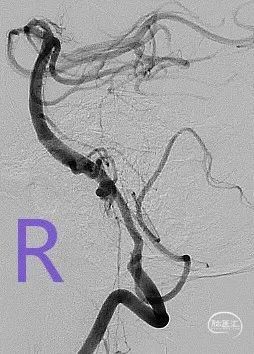

DSA结果:左侧P2段动脉瘤,约1mm*0.8 mm,颈宽约0.8mm,形态不规则。

术前影像DSA、DSA 3D

该病例为左侧大脑后动脉P2段微小宽颈动脉瘤,动脉瘤体直径仅0.9mm,载瘤动脉近端血管直径约1.7mm,远端血管直径约1.1mm,且双侧椎动脉均扭曲明显,但左侧后交通动脉粗大,考虑通过左侧后交通动脉为治疗路径,路途遥远,后交通的成角使得微导丝、微导管的操控存在一定难度;由于动脉瘤体小,因此微导管顺利进入动脉瘤腔内并保证安全是手术的关健点;支架微导管系统成功超选进入P3段远端也是手术成功的关键,对于支架的输送性和贴壁性要求极高。